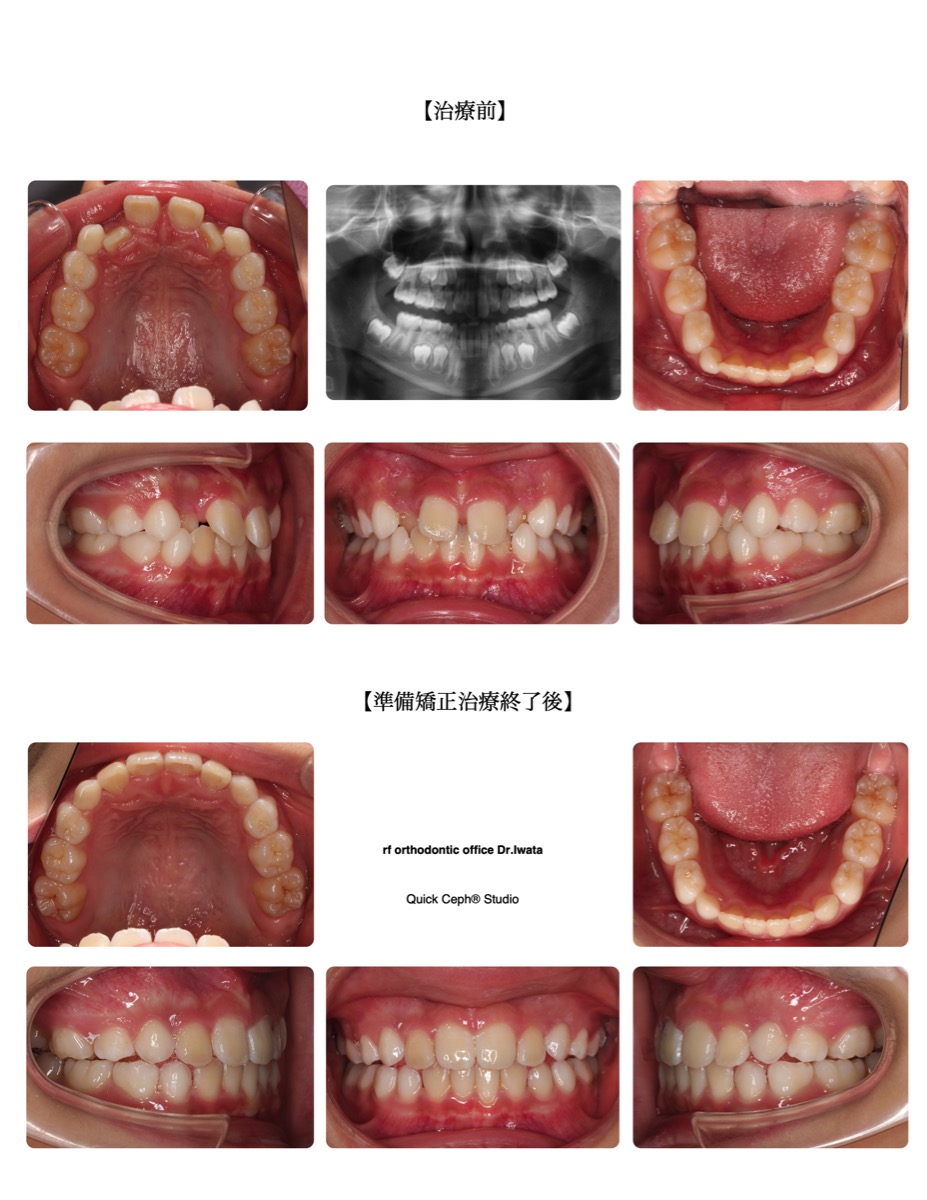

【主訴】前歯がすきっ歯で横の歯が内側から出てきた。

【主な症状】叢生

| 治療方法 | マウスピース型矯正装置 |

| 治療期間・回数 | 9ヶ月・11回 |

| 性別 | 男性 |

| 年齢 | 9歳 |